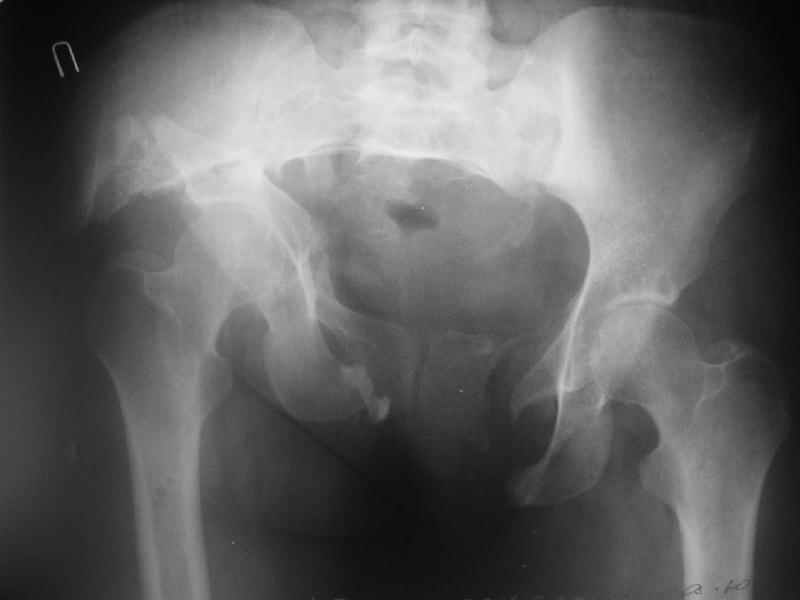

Дополнительно сообщаю, что больную беспокоят боли в области левого крестцово-подвздошного сочленения, в области правого болей нет. Кроме того, беспокоит укорочение конечности (ходит с компенсацией) без дополнительной опоры (в помещении), нарушение осанки (сколиоз, избыточный поясничный лордоз), боли в пояснице, невозможность стоять более 20-30 минут, спать без резинового круга под крестцом и подушкой под коленями, неудобство при сидении. Majeed 41 балл.

По просьбам коллег отправляем снимки таза: прямая, inlet, outlet, 2 дополнительные компьютерные томограммы.